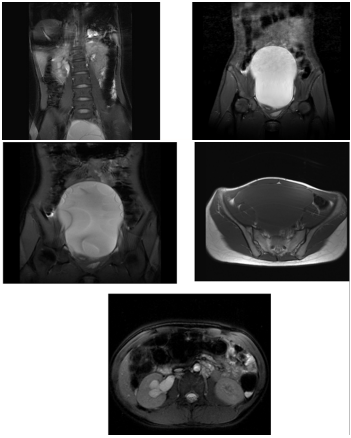

MRI of the pelvis

- A huge cystic mass measuring about 18x11cm is seen arising from the left ovary and displacing the uterus to right side.16

- Multiple thin septa are noted within the mass, no solid component seen, normal Right ovary seen, no adrenal mass, the right kidney shows hydronephrosis and hydroureter probably caused by back pressure from the ovarian mass, normal left kidney and other organ.17

Conclusion

The findings are suggestive of ovarian cystadenoma…